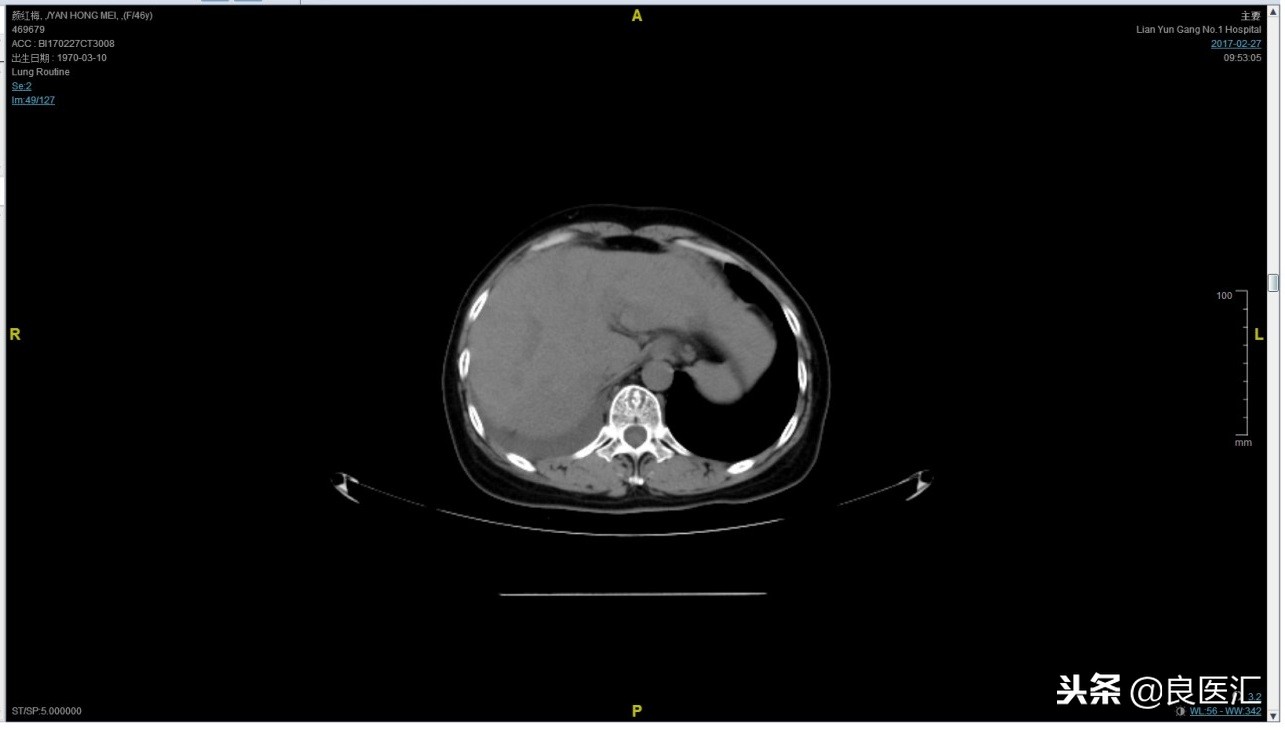

2017-02-27患者因气喘胸闷再次就诊。患者肺部病灶进展,同时出现肝脏转移。再次给予曲妥珠单抗+长春瑞滨化疗一周期,效果不佳,推荐换用TKI治疗,患者放弃治疗。PFS3=12个月。

总结